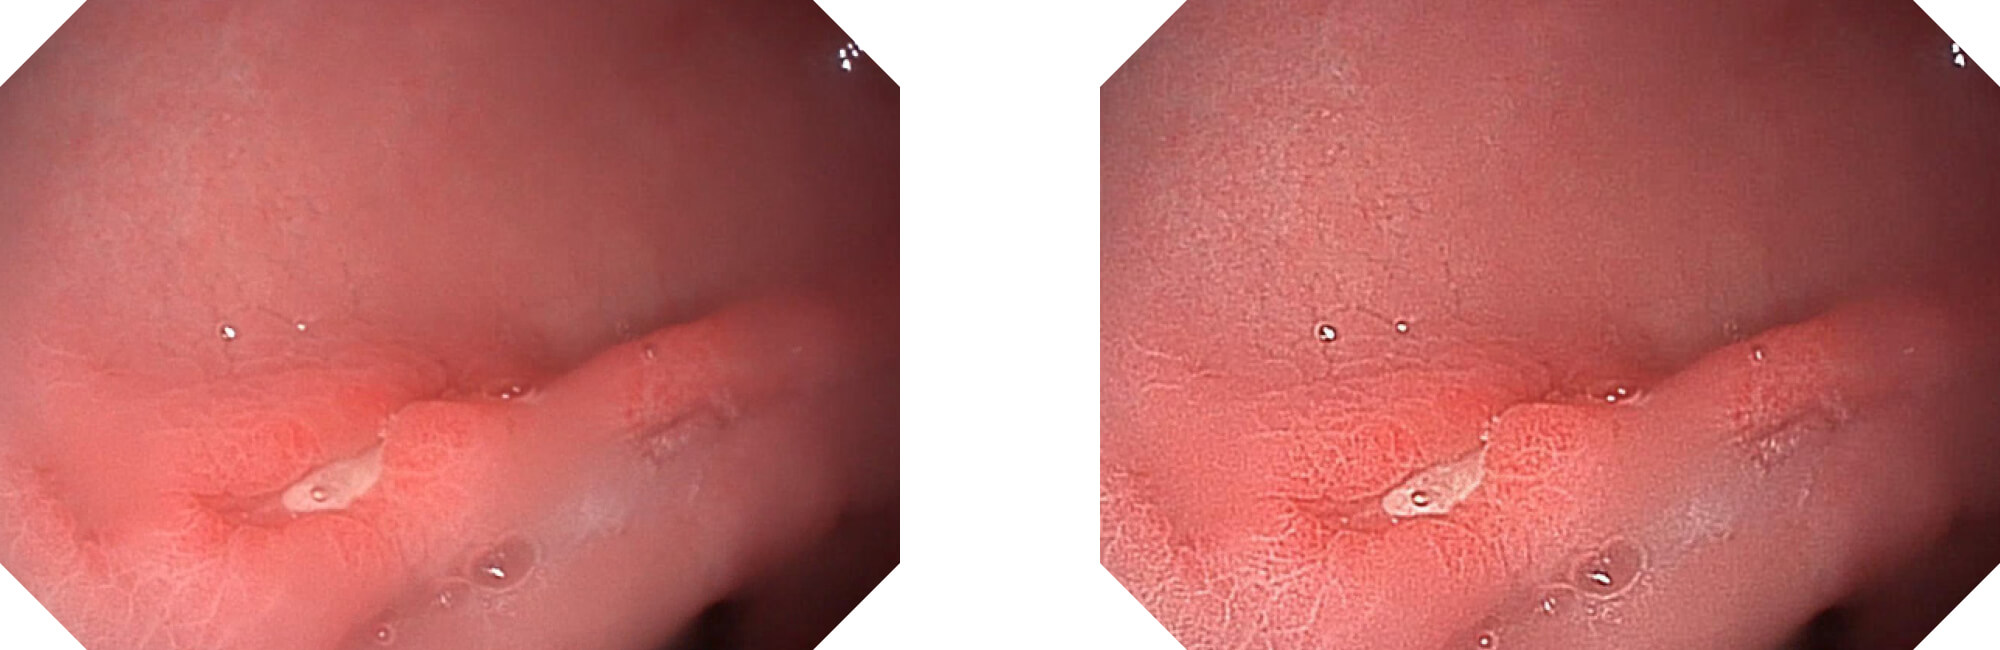

高清数字信号结合构造强调和色彩增强,多重图像处理技术能让每一个图像都清晰可见。

构造强调

色彩增强

电子放大

(Versatile Intelligent Staining Technology)

利用了血红蛋白在不同波长吸收下系数不同的原理,设计的一种光学域滤波和数字域滤波结合的染色技术,既保证了图像亮度,又可增强黏膜血管的对比度,充分凸显早期病变的细微结构变化,为临床疾病的观察诊断提供更丰富的参考信息。